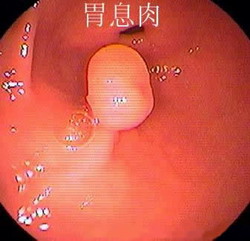

什么是胃息肉? 胃息肉(gastric polyp)是指胃黏膜局限性良性隆起病變。息肉這一名稱不表示它的病因及組織學(xué)構(gòu)造,只表示肉眼觀察到的隆起物。 胃息肉的病因: 目前病因不明。胃息肉是指起源...

胃息肉 分為增生性息肉和腺瘤性息肉。增生性息肉一般較小,癌變率較低;而腺瘤性息肉一般體積較大,多有家族遺傳性,癌變率高。胃息肉的發(fā)生率隨年齡增加而上升,大約三分之二的胃息...

胃息肉,是起源于胃黏膜上皮細(xì)胞凸入胃內(nèi)的隆起性病變。胃息肉較小時(shí)常無明顯癥狀,一般都是在胃腸鋇餐造影、胃鏡檢查或其他原因手術(shù)時(shí)偶然發(fā)現(xiàn)。我們知道,在胃癌的癌前病變中,就有...